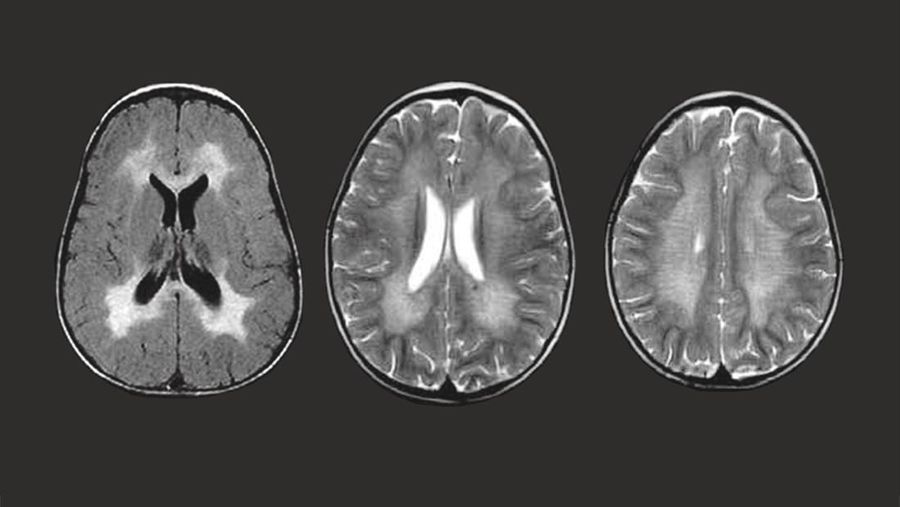

Foto: Penyakit Metachromatic Leukodystrophy. (Dok. mldsupportuk)

Laman resmi Children's Hospital of Pittsburgh menjelaskan MLD merupakan penyakit yang ditularkan dari orang tua ke anak melalui gen yang rusak. Cleveland Clinic menuliskan kondisi tersebut menyebabkan kerusakan pada otak dan sumsum tulang belakang serta saraf tepi.

Tubuh tidak bisa memproduksi enzim arilsulfatase A dengan baik pada mereka penderita MLD. Keadaan ini membuat mielin, lapisan khusus pelindung saraf tubuh menghilang yang akan membuat saraf berhenti bekerja.